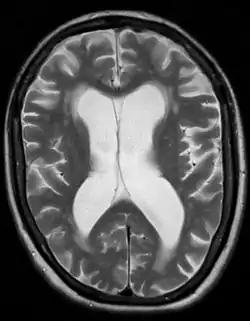

- Wodogłowie normotensyjne jest swoistą formą wodogłowia komunikującego, w którym dochodzi do powiększenia komór mózgu bez znacznego wzrostu ciśnienia płynu mózgowo-rdzeniowego. Da się je zdiagnozować jedynie prowadząc ciągły pomiar ciśnienia płynu (w przeciągu 24 godzin lub dłużej), ponieważ inne metody pomiaru nie wykazują w ogóle podwyższonego ciśnienia. Pomiary elastyczności komór mogą być również pomocne w diagnostyce tego typu wodogłowia. Zmieniona elastyczność komór i podwyższona lepkość płynu mózgowo-rdzeniowego mogą pełnić istotną rolę w patogenezie wodogłowia normotensyjnego.

- Wodogłowie ex vacuo odnosi się do poszerzenie układu komorowego i zwiększenia objętości płynu mózgowo-rdzeniowego wtórnie do zaniku miąższu mózgu. Może być wywołane atrofią mózgu (np. w demencji), pourazowym uszkodzeniem mózgu a nawet zdarza się przy niektórych zaburzeniach psychiatrycznych (np. w schizofrenii)[10]. W przeciwieństwie do pozostałych typów wodogłowia jest to tylko kompensujące powiększenie komór mózgu i nie jest ono wywołane wzrostem ciśnienia płynu mózgowo-rdzeniowego.[10]

Wodogłowie rozpoznaje się na podstawie palpacyjnej oceny napięcia i wielkości ciemiączek, szerokości szwów czaszkowych, pomiarów obwodu główki odpowiednio do wieku na siatkach centylowych. Badaniem obrazowym, wykonywanym w pierwszej kolejności, jest ultrasonografia przezciemiączkowa, ewentualnie tomografia komputerowa lub obrazowanie metodą rezonansu magnetycznego.